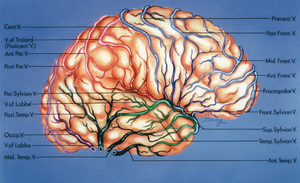

A. cerebri media

A. Cerebri media (ACM) forsyner den superiore og den laterale flade af temporallappen, samt den laterale del af den inferior flade. ACM inddeles i segmenter fra M1 (medias hovedstamme) til M4 perifert. M4 grene af media løber over lateralfladen af temporallappen fra M3 grene i lateralfissuren henover T1 videre til T2 og videre til T3 (Fig. 7). Det er derfor essentielt at beskytte M4 grenene eksempelvis ved operation i gyrus superior (T1) for at undgå iskæmsike skader i T2 og T3. Når lateral fissuren spaltes møde man først M3 grene af a. cerebri media som stiger op gennem lateral fissuren fra M2 grene der forløber på Insulas overflade. Følges disse anteriort når man til deres oprindelse fra M1 = medias hovedstamme, hvor overgangen fra M1 til M2 er beliggende svarende til Limen Insula.